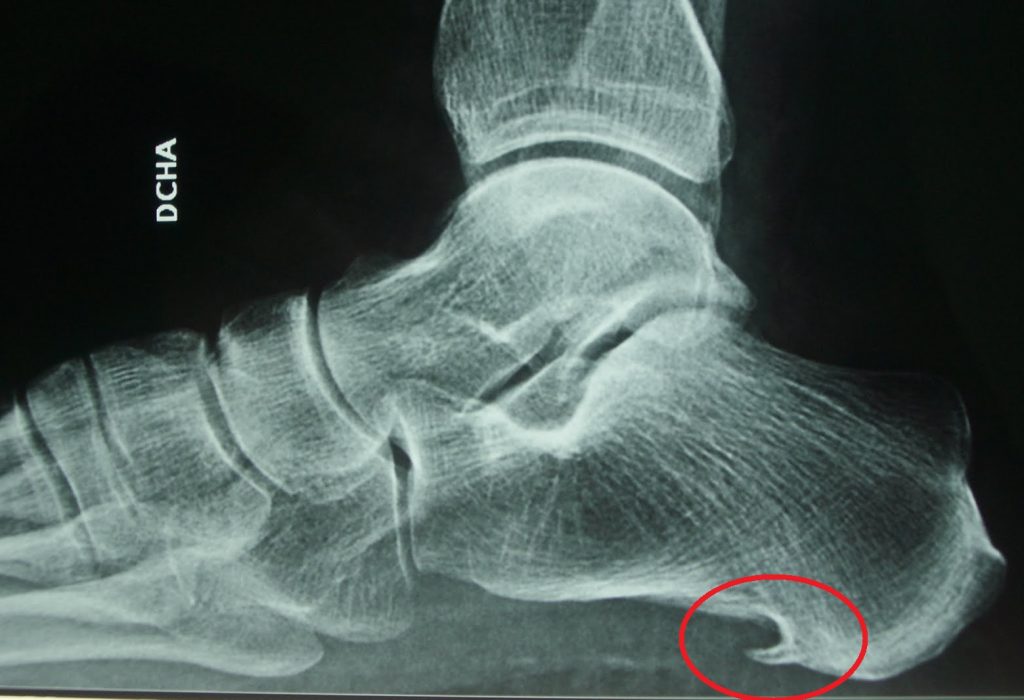

En primer lugar, se realiza un examen físico del pie del paciente que, si sufre una fascitis plantar, evidenciará hinchazón, enrojecimiento de la zona y sensibilidad a la presión en el talón. En algunas ocasiones, si el dolor es muy intenso, podemos solicitar una ecografía para descartar una microrotura o rotura parcial de la fascia plantar. Si se solicitan radiografías se pueden ver en algunos casos la presencia de espolón pudiendo observarse también fascitis plantar. En cualquier caso, existen individuos que presentan fascitis plantar y no se visualiza ningún espolón calcáneo en su radiografía.